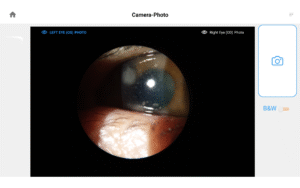

Pushing ahead, our imaging system includes our new, patent-pending Halo background light. Working with native slit lamp illumination, Halo delivers unparalleled clarity of the ocular adnexa. You’ll uncover details of the meibomian glands, acinar spaces, conjunctiva, lid margins, and lashes like never before.

CPT / HCPCS Code 92285 External ocular photography with interpretation and report for documentation of medical progress, (eg close-up photography, slit lamp photography, goniophotography, stereo photography).